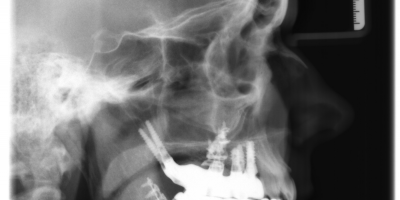

The patient of 55 years old was wearing a total prosthesis, he was very unhappy and retention was bad.

Treatment option was surgery with ROOTT P (Pterygoid Implant) as the bone was soft, D3 cancellous bone, temporary bridge, impression after surgery, key, try-in of the frame and placement. All screw retained with angulated screw channel.